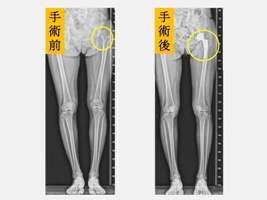

黃贊文部長表示,陳小姐因為長年疼痛和不能好好參加小孩的社團發表、學校活動讓她看起來非常憂鬱,也轉介給身心科醫師一同協助。陳小姐左側髖關節和大腿因為曾經手術2次有著長達30公分疤痕,肌肉也有明顯的萎縮,因此建議進行「微創正前開髖關節置換手術」。陳小姐在手術當天下午麻醉藥效一退,就開始練習騎腳踏車運動,陳小姐說,原本以為會很痛,但完全沒有痛的感覺,2隻腳也一樣長了,腳踩在地上的感覺非常不真實,就像是睡了一覺做了一個夢,很擔心萬一夢醒了怎麼辦?當下激動到眼角泛淚。

黃贊文醫師指出,髖關節發育不良導致的髖關節炎一般好發在40至55歲,女性居多。若在兒童時期就診斷出來,可進行髖關節截骨矯正手術來促使髖關節得以正常發育;若是在成年後發現有初期的髖關節炎也可以藉由髖關節截骨矯正手術來延緩置換人工關節的時間;但若已進展到末期,治療的方式則是直接安排人工髖關節置換手術。